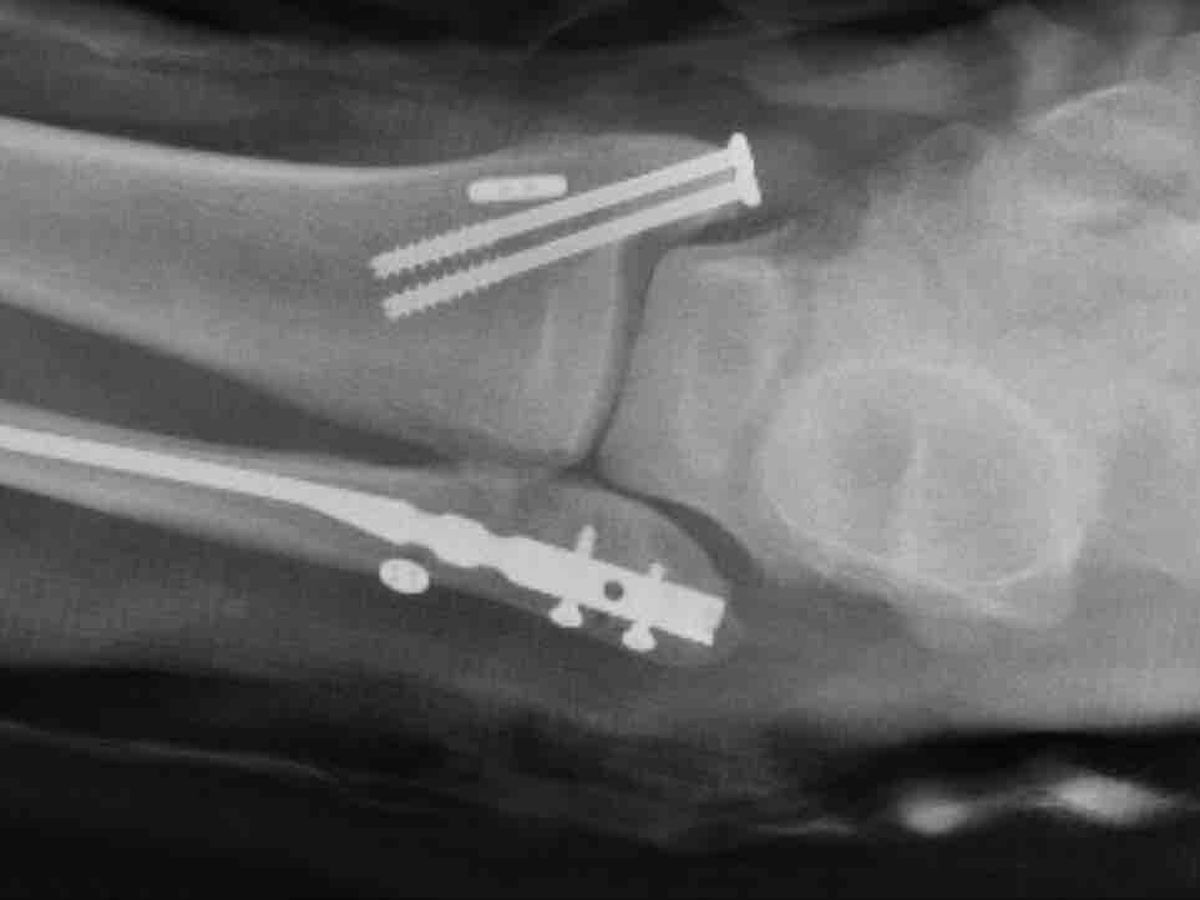

Hello, Matthew is the most kind person you will ever meet has the biggest heart.He loves the game and was born to play it, he literally eats, sleeps and breathes hockey. Matt is one to never ask for help, he is the one who is always helping others and go in the extra mile, he definitely is not used to sitting on the couch, being waiting on hand and foot. So this time around it’s the opposite. We are asking for help because even though we have insurance he is going to be out of work for a long time on the road to recovery, so we are asking for donations to help offset the cost of medical bills to come. Matthew maybe a quite person and not talk much, but you give him hockey skates and ice and he turns into a little kid in a candy store.Today while participating in a tournament in Pittsburgh he took a fall and found out that his ankle is broken in three different places and he is going to need two-three surgeries, we don’t know how long he is going to be out of work, recovery time and medical bills. I am seeking help from family, friends etc to help us with these huge expenses we are going to endure in the next months to come. I graciously appreciate everyone who can help, no amount is to small Thank you all in advance and we love you